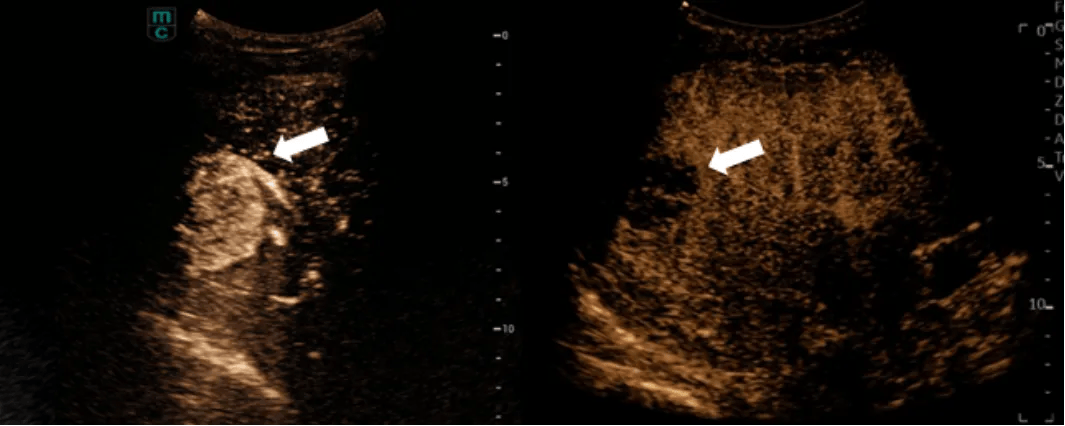

右图为病灶治疗后超声造影显像情况

首次手术共有两名原发性肝癌患者接受了超声组织碎化术治疗。治疗在中国工程院院士、北京清华长庚医院院长董家鸿和美籍专家的指导下,由肝胆胰外科主治医师黄鑫主导完成。每位患者治疗时间不到半小时。术后病灶超声造影显像无强化,即肿瘤在造影剂下已没有变亮显影,患者肿瘤周边的肝脏血管、胆管等脉管未受到损伤。